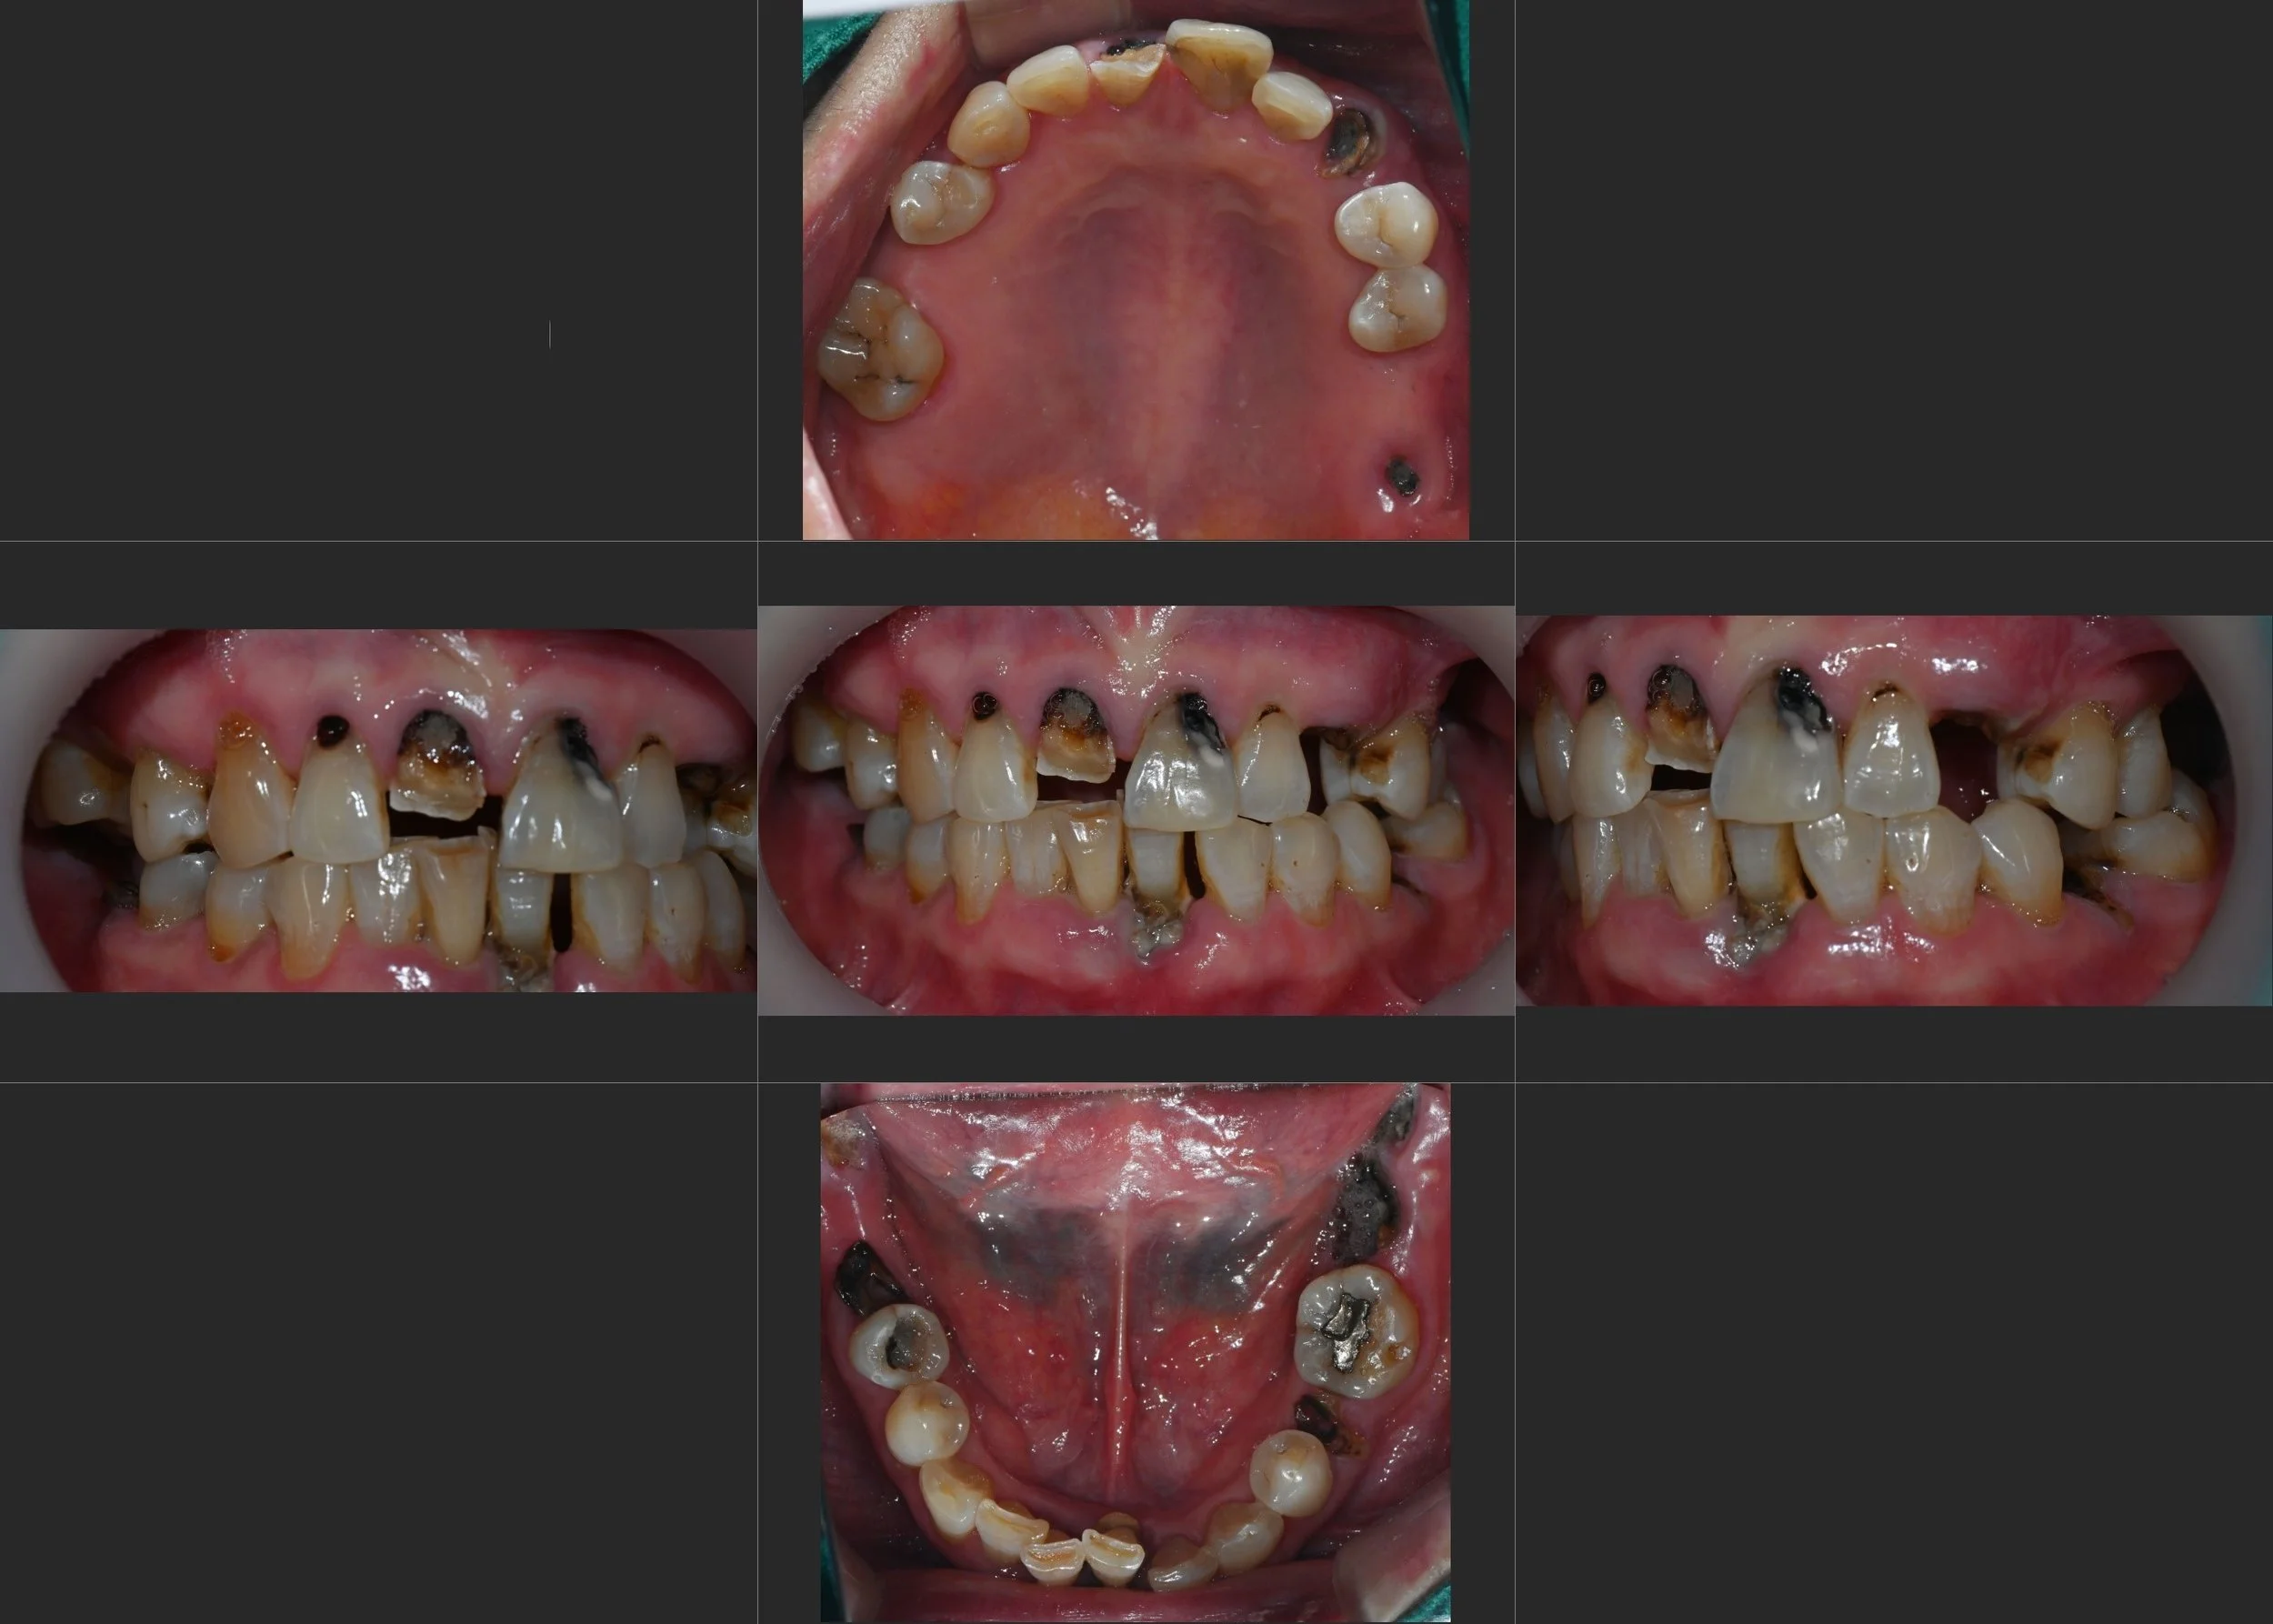

A female patient in her 50s presented with significant functional impairment due to extensive tooth loss, generalized severe periodontitis, and multiple dental caries. Her occlusal plane was completely collapsed, leading to an unstable bite and reduced chewing efficiency.

OPG - BEFORE

INTRA ORAL - BEFORE